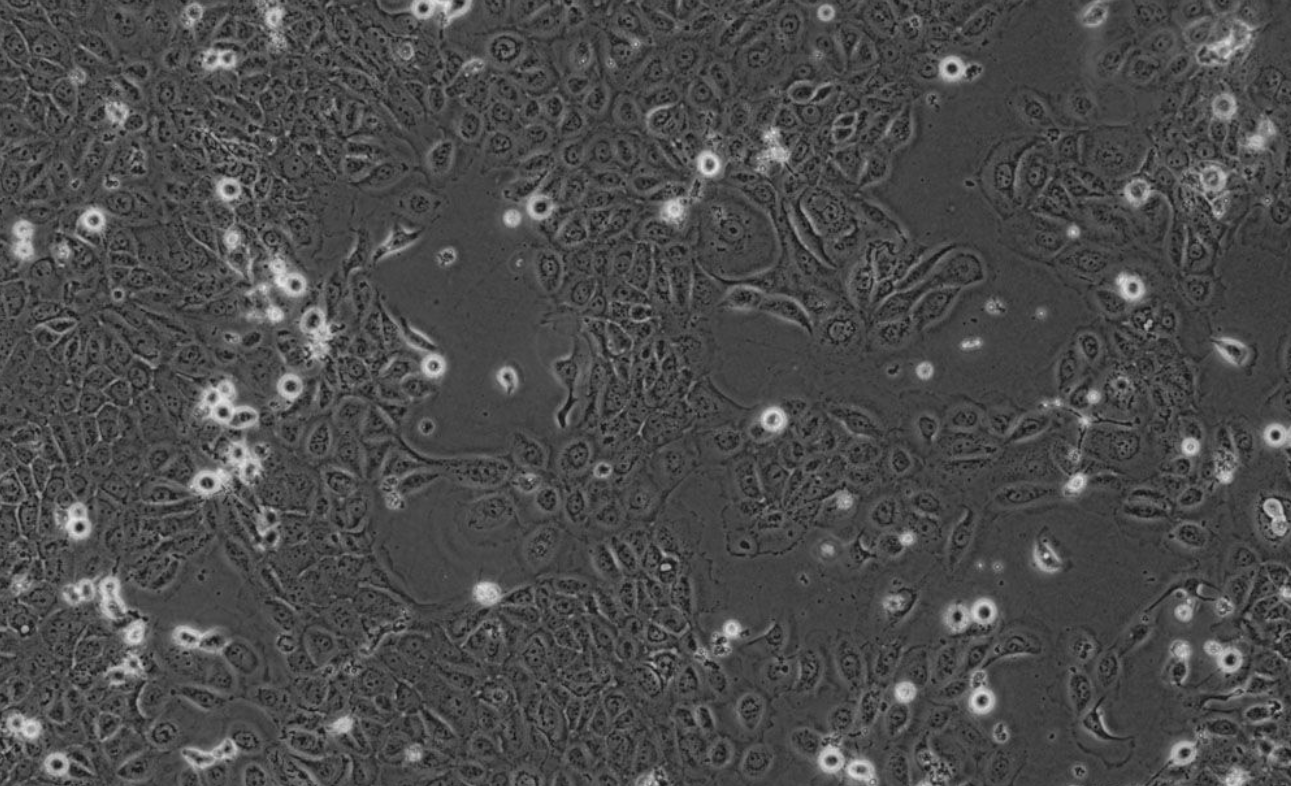

形态 |

上皮细胞样 |

生长特征 |

贴壁生长 |